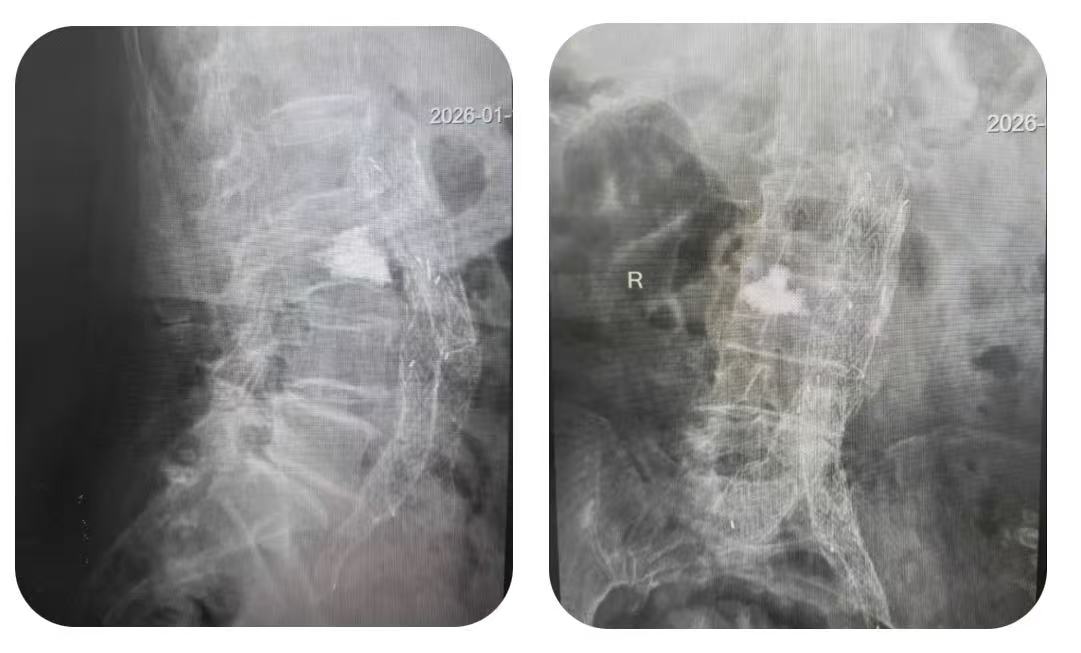

为确保手术安全,科室启动多学科协作机制,联合麻醉科、放射影像科进行术前会诊,共同制定个体化麻醉方案与精准影像引导路径。手术在基础麻醉和局部麻醉下进行,在实时影像引导下,医生经皮穿刺建立微小通道,将球囊精准置入压缩的腰三椎体内,并缓慢扩张球囊复位椎体,随后注入骨水泥强化椎体稳定性。手术创口微小,过程顺利,术中出血少、耗时短,患者未出现任何并发症,真正实现“微创、精准、安全”。